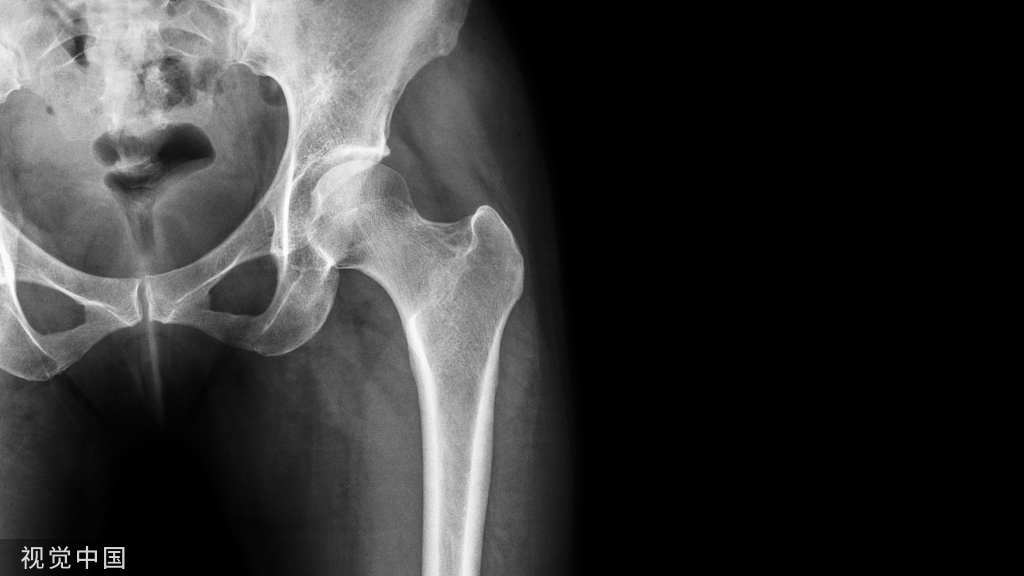

体表标志和切口

2切口

屈髋30°并内收可以越过对侧膝关节,既可以使大转子放松,也可以使阔筋膜张肌移向前方。以大转子尖端为中心做一8~15cm长的纵向直切口。切口长度与患者的肥胖程度和身体大小以及术者经验有关。切口通过大转子后方1/3向下延伸至股骨干。